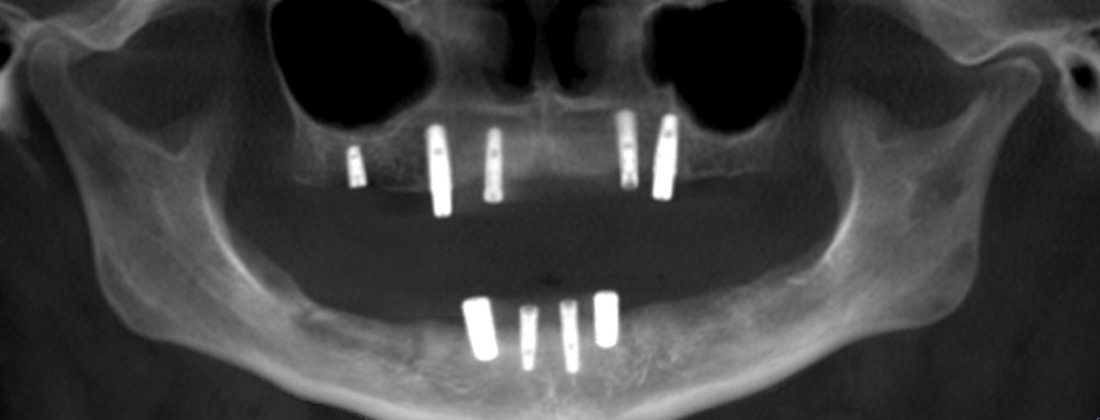

Fusion Dental Implant Club Redo All-on-X Case Example